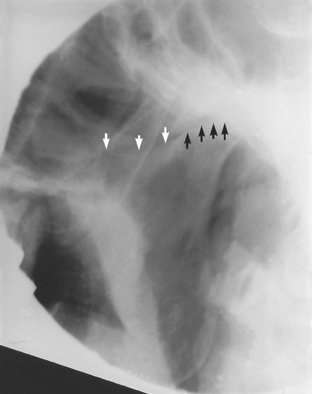

Page 237

This is a temporomandibular disorder in which radiography helps to confirm the diagnosis. There may be erosion, osteophytes or traction spurs in active disease (Fig. 16.8) and marked irregularity of the condylar surface in the resolving phase.

image

Fig. 16.8 Radiograph illustrating degenerative joint disease. Both condyles have a flattened, irregular superior surface; there is an active erosion centrally in the right condyle.

The TMJ may be affected by a wide variety of systemic arthropathies. The juvenile form of rheumatoid arthritis can be very destructive, but fortunately the adult form is rarely so. Ankylosing spondylitis, reactive arthritis, gout, systemic lupus erythematosus and psoriatic arthritis are all seen in the TMJ periodically and all have the capacity to cause permanent damage to joint surfaces with loss of condylar height (Fig. 16.9). Reactive arthritis seems particularly prone to causing adhesions in the joint.

Fig. 16.9 Radiograph showing destruction of the condyle due to ankylosing spondylitis. White arrows show the sigmoid notch, the black arrows show the margin of what remains of the condyle.